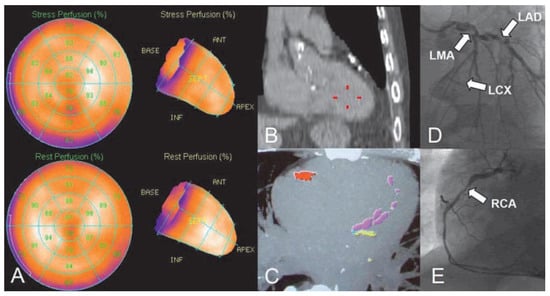

Kardiale Hybrid-Bildgebung in der Diagnostik der koronaren Herzerkrankung

by Oliver Gaemperli and Philipp A. Kaufmann

Cardiovasc. Med. 2011, 14(3), 75; https://doi.org/10.4414/cvm.2011.01572 - 23 Mar 2011

CT coronary angiography and myocardial perfusion scintigraphy are both established non-invasive techniques for the diagnosis of coronary artery disease (CAD). Cardiac hybrid imaging consists of the combination (or “fusion”) of both modalities and allows obtaining complementary morphological (coronary anatomy, stenoses) and functional (myocardial [...] Read more.

CT coronary angiography and myocardial perfusion scintigraphy are both established non-invasive techniques for the diagnosis of coronary artery disease (CAD). Cardiac hybrid imaging consists of the combination (or “fusion”) of both modalities and allows obtaining complementary morphological (coronary anatomy, stenoses) and functional (myocardial perfusion) information in a single image. The appropriate clinical use of hybrid imaging requires its integration into joint clinical diagnostic services where experts in all fields (cardiology, radiology, nuclear medicine) collaborate and colleagues with clinical and technical expertise together can exploit the potential of the new technique. The feasibility and clinical value of hybrid imaging has been documented in small cohort studies and selected series of patients. The incremental value of the hybrid technique arises from the spatial coregistration of perfusion defects with coronary stenoses. This allows to assess the haemodynamic relevance of coronary stenoses and determine the need for revascularisation procedures in each individual artery. The combination of the (native) coronary artery calcium score scan with MP-SPECT can also be helpful in different clinical scenarios. Thus, it can be anticipated, that the ongoing efforts to reduce radiation exposure and the increasing clinical interest will further pave the way for an ever increasing use of cardiac hybrid imaging in clinical practice. Full article